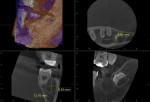

The parent informed the providers that a 3-dimensional CBCT scan was acquired at a previous dental office. This CBCT scan was thus requested and reviewed by a board-certified oral and maxillofacial radiologist who was part of the authors' team at MWU. The limited field-of-view CBCT scan, acquired on a Veraview X800 (J. Morita, morita.com), was received and showed teeth Nos. 17, 18, and the distal half of No. 19. Well-defined, circular, corticated, homogeneous radiolucency, approximately 12 mm x 8 mm x 9 mm, with no internal contents was observed on the buccal aspect of tooth No. 18 (Figure 3). Vertically, the radiolucency extended from the alveolar crest to the level of root apices. The roots of tooth No. 18 appeared to be displaced lingually, with a slight buccal inclination of the tooth crown. No displacement of the left mandibular canal was observed (Figure 4).